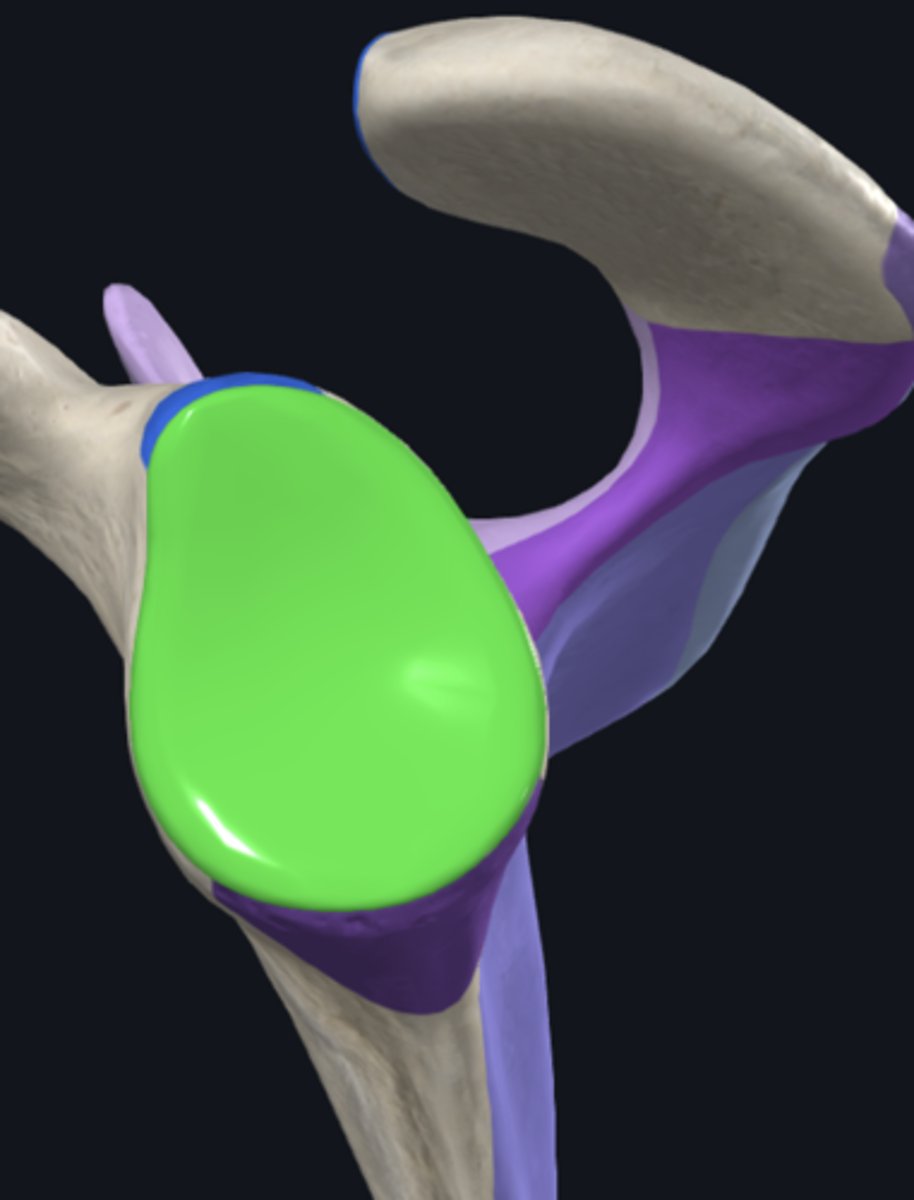

Acromion

Coracoid process

glenoid fossa

infraglenoid tubercle

infraspinous fossa

spine of scapula

supraglenoid notch

subscapular fossa

supraglenoid tubercle

supraspinous fossa